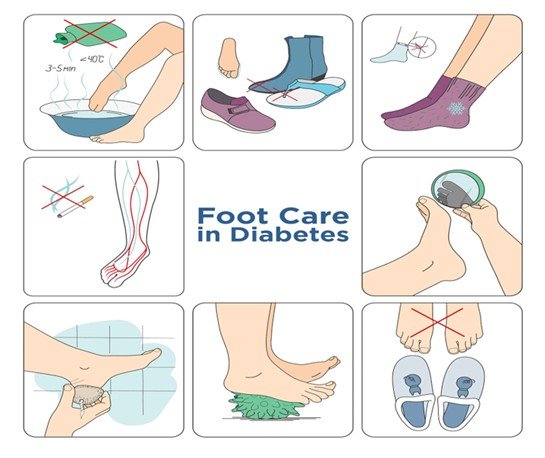

The management of diabetic foot ulcers involves a mix of prompt medical attention, enhanced treatment solutions, and self-management. After attentive wound healing, blood sugar management, and prevention, patients can significantly enhance outcomes and decrease the risk of severe complications. Preventive care and suitable treatment are the only way to keep feet healthy and well.